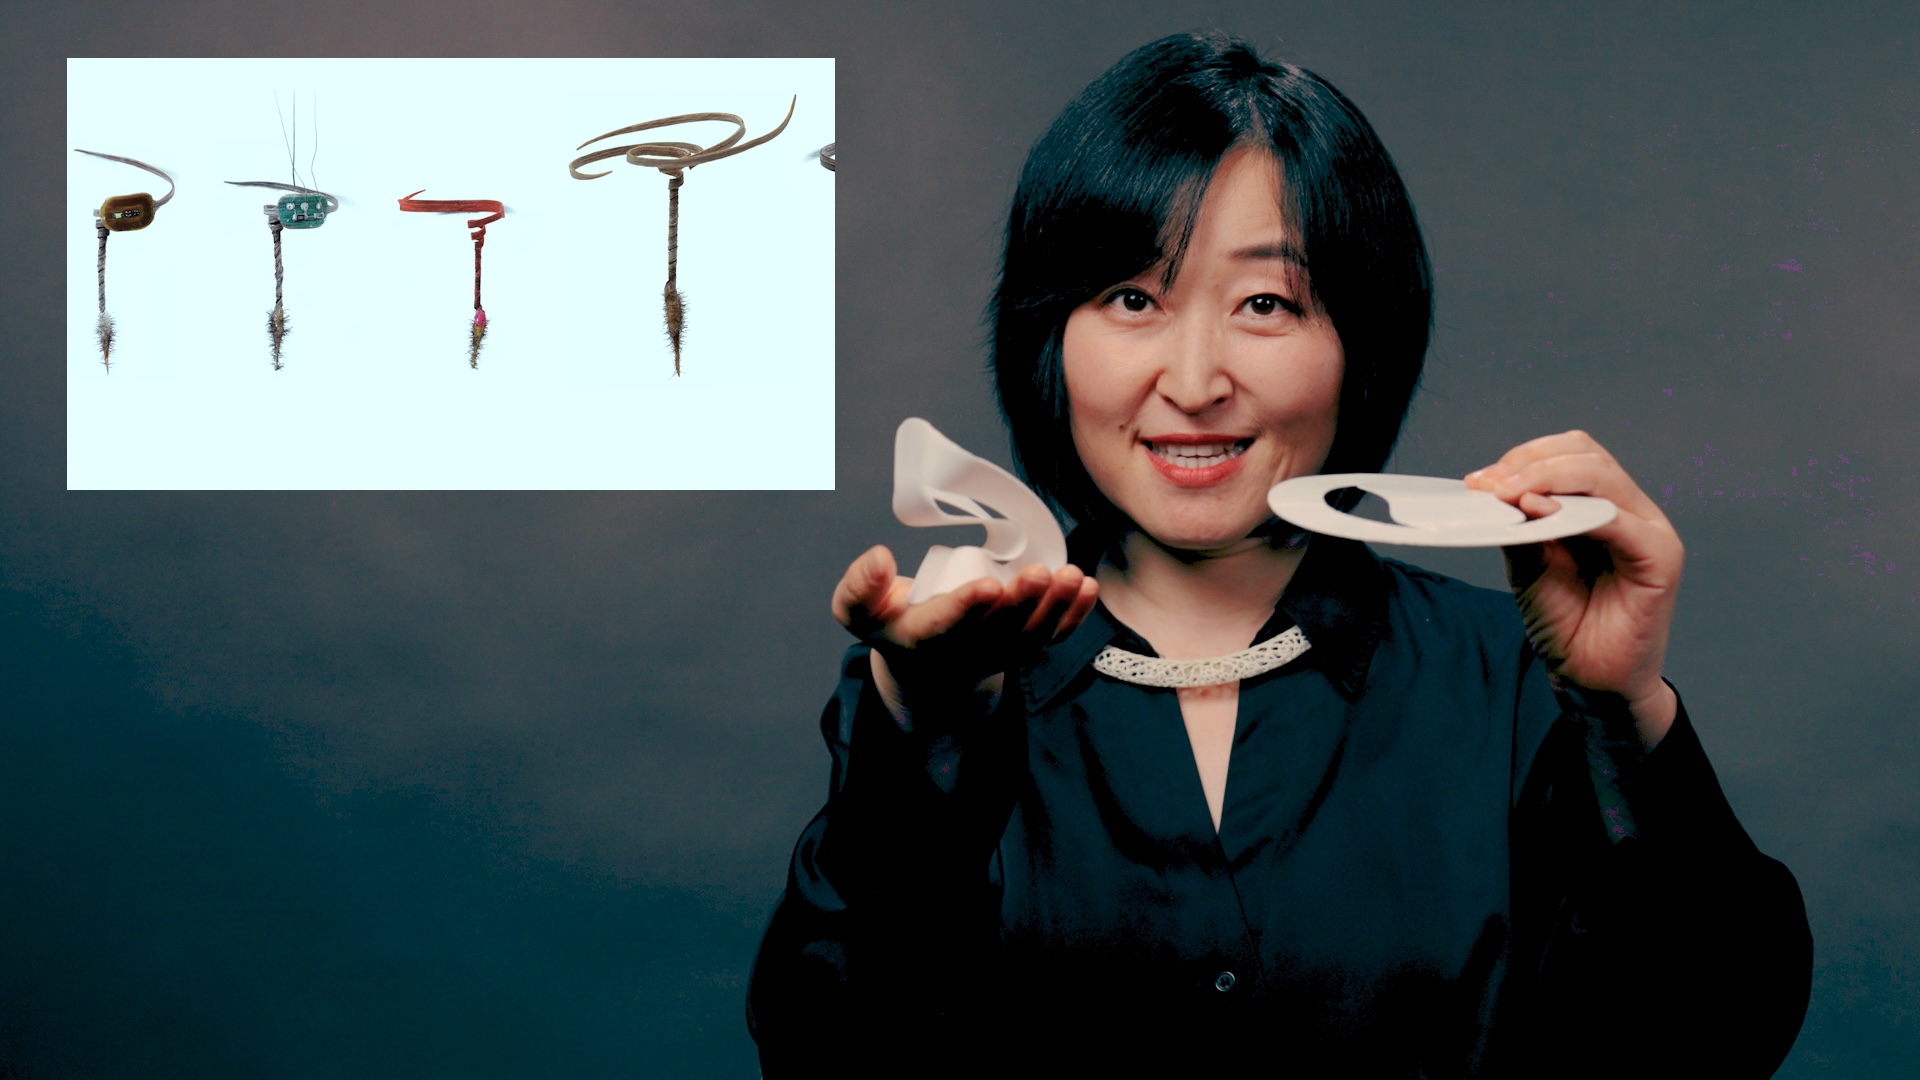

From COVID to cancer, new at-home test spots disease with startling accuracy

A new technology created by UC Berkeley engineers uses the “coffee-ring effect,” paired with plasmonics and AI, for rapid diagnostics.